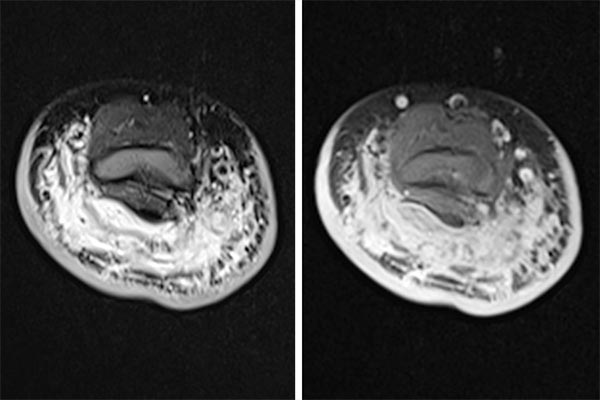

MRT Bildgebung (links – TIRM-Sequenz, rechts – dynamische MR-Angiographie). Nachweis unscharf begrenzter Signalanhebungen des dorsalen Oberarmes durch den Tumor mit senkrecht zur Haut verlaufenden hyperintensen Septen, entsprechend einem ausgedehnten lokalen Lymphödem. In der dynamischen MR-Angiographie Nachweis eines in der arteriellen Kontrastmittelphase hyperperfundierten Tumors mit klar erkennbaren arteriellen Feedergefäßen aus der A. brachialis.

MRT-Bildgebung (links TIRM-Sequenz, rechts T1-Wichtung mit spektraler Fettsättigung nach Gadoliniumgabe). Darstellung der diffusen Infiltration des dorsalen Oberarmes mit charakteristischer Verdickung der Kutis, subkutan betontem Lymphödem sowie diffuser Kontrastmittelanreicherung des Tumors, die schwer von einander abzugrenzen sind. In Zusammenschau von Laboruntersuchung, klinischem Befund sowie MRT-Bildgebung wurde die Diagnose eines kaposiformen Hämangioendothelioms gestellt.